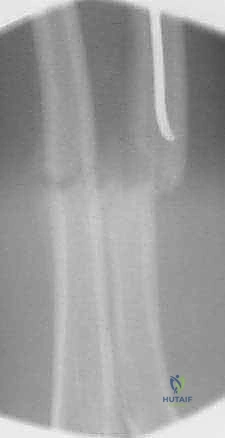

التشخيص الشعاعي الدقيق

في عيادة الأستاذ الدكتور محمد هطيف، لا يتم الاعتماد على الفحص السريري فقط. يُعد التشخيص الشعاعي الدقيق حجر الزاوية في تحديد خطة العلاج:

- الأشعة السينية (X-rays): يتم أخذ صور بأوضاع مختلفة (أمامي خلفي AP وجانبي Lateral). يصر الدكتور هطيف دائماً على أن تشمل الأشعة المفصل الذي يعلو الكسر (الكوع) والمفصل الذي يليه (الرسغ) لضمان عدم وجود كسور أو خلوع خفية (مثل كسور مونتيجيا أو جاليازي).

تُعد تقنية التثبيت بالمسامير المرنة داخل النخاع (Flexible Intramedullary Nailing - FIN) أو مسامير التيتانيوم المرنة (Titanium Elastic Nails - TENs) المعيار الذهبي (Gold Standard) لعلاج كسور الساعد غير المستقرة لدى الأطفال. والأستاذ الدكتور محمد هطيف هو رائد هذه التقنية في اليمن.

يتم إدخال مسمارين مرنين (عادة من التيتانيوم أو الصلب الطبي المقاوم للصدأ) داخل التجويف النخاعي (Marrow Canal) للعظم. يتم ثني هذه المسامير مسبقاً بواسطة الجراح لتشكيل قوس. عندما يتم إدخالها في العظم، فإنها تعمل بمبدأ "التثبيت ثلاثي النقاط" (Three-Point Fixation). تولد المسامير المرنة قوة شد داخلية تدفع أجزاء العظم المكسور نحو بعضها البعض، مما يوفر استقراراً حيوياً ميكانيكياً (Biomechanically Stable) يسمح بتكوين الكالس (Callus) وشفاء العظم بسرعة فائقة.